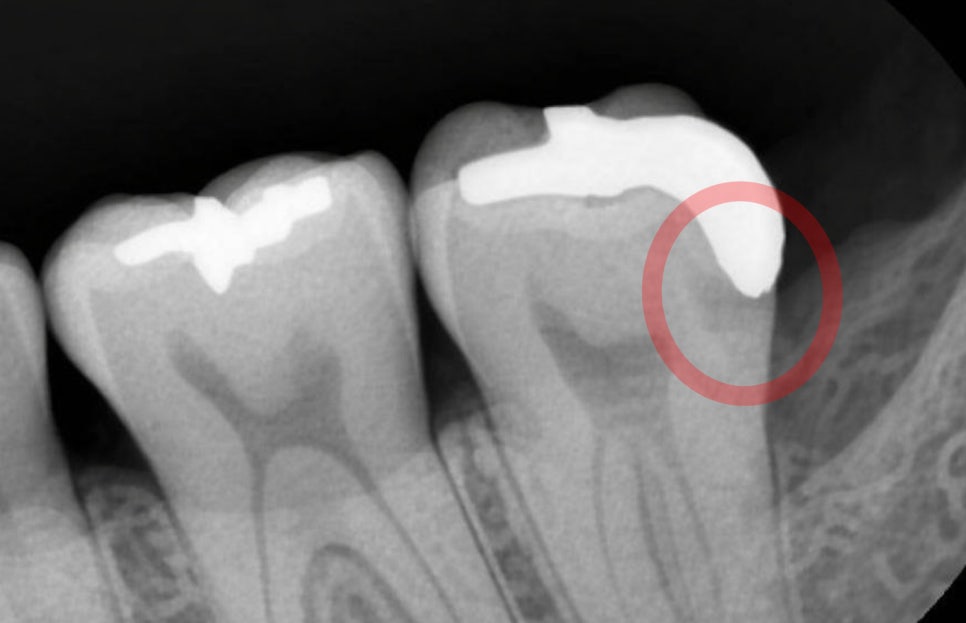

시간이 흐르면서 보철과 자연치가 맞닿는

경계 부위에 틈이 벌어지면

이 틈을 통해 세균이나 음식 찌꺼기,

타액이 반복적으로 스며들 수 있고

그 결과 크라운 아래에서

우식이 다시 시작될 수 있습니다.

겉으로 잘 드러나지 않을 때가 있기 때문에

환자 스스로 인지하기 어렵다는 특징이 있으며

초기에는 통증 또한 거의 없기 때문에

정기 검진을 통해서만 발견할 수 있습니다.

특히 크라운을 씌운 곳은

보철을 제거하기 전까지

정확한 상태를 확인하기 어려우며

그 결과 치질이 약해지고

결국 치수까지 감염되거나

치근단 염증으로 이어질 수 있으며

재수복만으로는 해결이 어려워집니다.

경우에 따라서는 자연치를 보존하지 못하고

발치로도 이어질 수 있으며